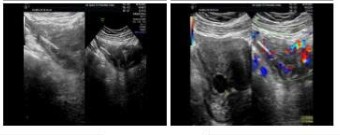

- Siêu âm tử cung phần phụ: phát hiện khối viêm kích thước 6x5 cm cạnh tử cung phải, nghi áp xe phần phụ, bên trong có vật cản âm nhỏ nghi dị vật.

Hình ảnh siêu âm: dị vật cản âm hình que nằm trong vòi trứng phải

(Nguồn: Bệnh viện Quốc tế Phương Châu)